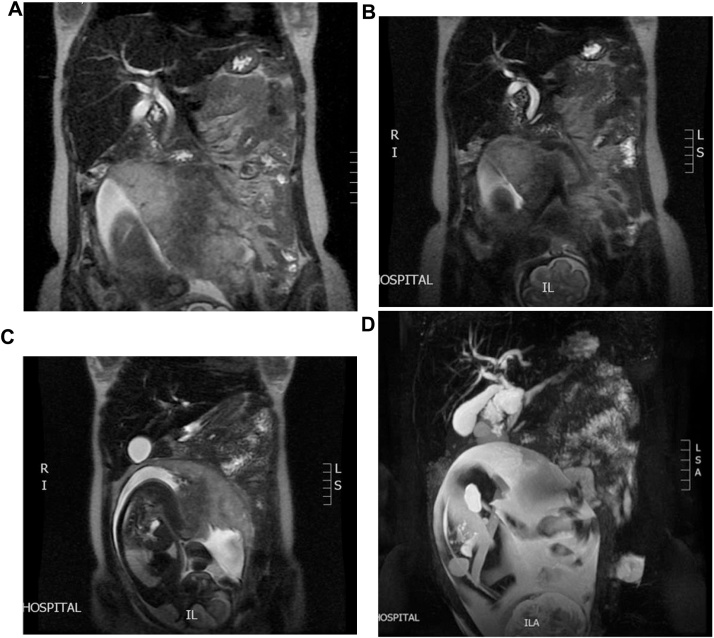

We report a case of a 22 years old pregnant female medically free, referred to us from her Obstetrician when she was complaining of abdominal pain and jaundice. Abdominal US confirmed a single intrauterine pregnancy at 28th week of gestation with appropriate growth for date and showed dilated intrahepatic ducts otherwise it was inconclusive due to the gravid uterus (Fig. 1). Her blood investigations showed a picture of cholestatic jaundice, and all other labs were within normal. So, we decided to proceed with a Magnetic resonance cholangiopancreatography (MRCP) which showed dilatation of both of the CBD (measuring 0.9 cm) & pancreatic duct, as well as an ampullary mass measuring 2 cm (Fig. 2). Later on, Endoscopic retrograde cholangiopancreatography (ERCP) with shielding of the abdomen to protect the fetus from radiation revealed an ampullary and distal CBD strictures. A punch biopsy was taken & the CBD was stented. The histopathology came as invasive adenocarcinoma & full metastatic work up was done and did not reveal any metastatic lesions. So, surgery was the best available option with the best possible outcome but we were reluctant to delay the surgery to ascertain the viability of the fetus. At 34th week of gestation induction of labor was done, both mother and the baby did well and were discharged home on 2nd day postpartum. The mother was readmitted one week later & full body CT scan repeated & there was no vascular invasion or distant metastasis.

There are different radiological modalities that can aid in obtaining a confirmatory diagnosis and staging of ampullary carcinoma but not all of these can be used freely during pregnancy such as ERCP or CT scan, due to the risk of radiation exposure to the fetus [ref. 7]. The main diagnostic modalities for pregnant women are ultrasonography and MRCP. The ultrasonography is mainly used to identify the presence of biliary dilation & obstruction while MRCP can visualize the mass [ref. 8].

In our case, the MRCP revealed an ampullary mass measuring 2 cm with no vascular involvement. ERCP is used during pregnancy for diagnosis by obtaining a biopsy, stenting for biliary draining and to prepare the patient for surgery or if the tumor is not operable. To minimize the risk radiation exposure to the fetus the patient should have a lead shield in place as we did in our case. Biochemically, an elevated carbohydrate antigen 19-9 (CA 19-9) level may help to guide the diagnosis towards an ampullary adenocarcinoma [ref. 4]. Nevertheless, US and MRCP were the main diagnostic modalities reported in the literature.